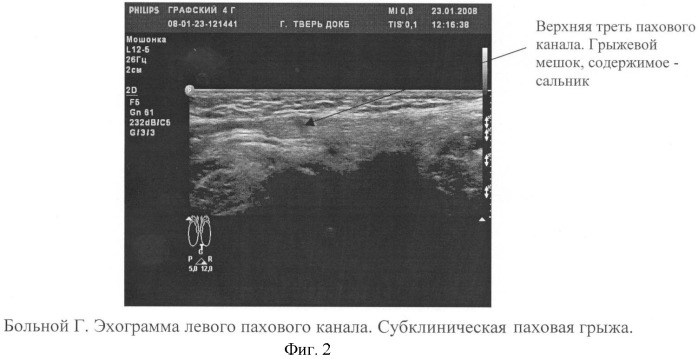

В МЦ «ОЛМЕД» при диагностике паховой грыжи пациента направляют на УЗИ мошонки и половых органов, а также на рентгенологическое исследование органов таза и паховой области. После этого опытные хирурги медицинского центра «ОЛМЕД» определяют характер грыжи и назначают лечение.

Диагностика паховой грыжи:

При этом у пациентов с ожирением возможно затруднение при выявлении грыжевого выпячивания. В отдельных случаях это требует проведения дополнительного обследования (УЗИ мягких тканей, МСКТ передней брюшной стенки) с целью подтверждения диагноза либо его исключения.